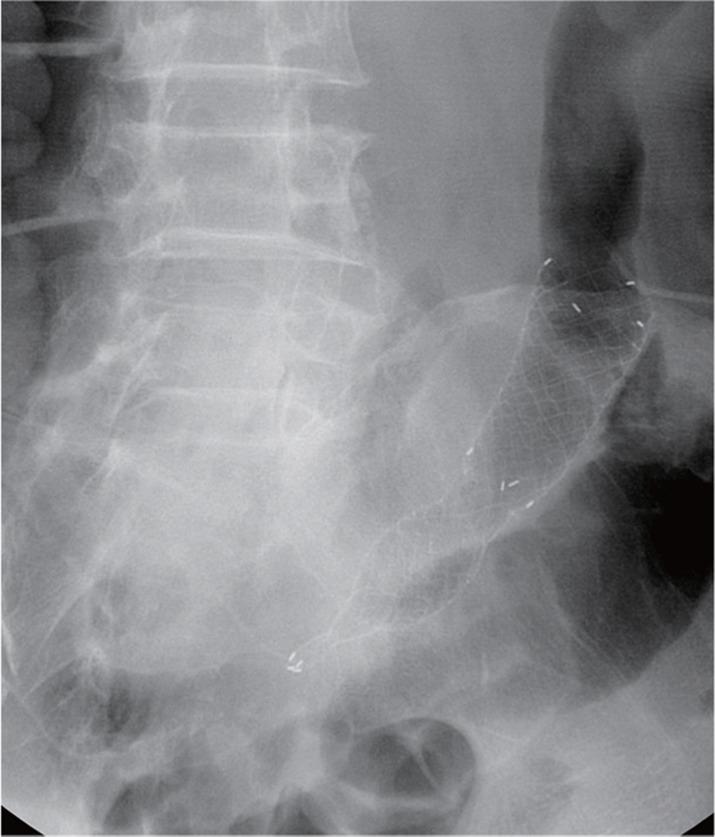

Successful management of colonic perforation with a covered metal stent.

Self-expandable stents are widely available for the treatment of perforation of the gastrointestinal tract. Because of the risk of migration, there has been no report of the use of self-expandable stents for the treatment of perforation of the colon or rectum. This is a report of successful treatment of iatrogenic colonic perforation during balloon dilatation of anastomotic stricture with a fully covered stent. Fully covered, self-expandable metallic stents can be considered useful tools for management of this condition.